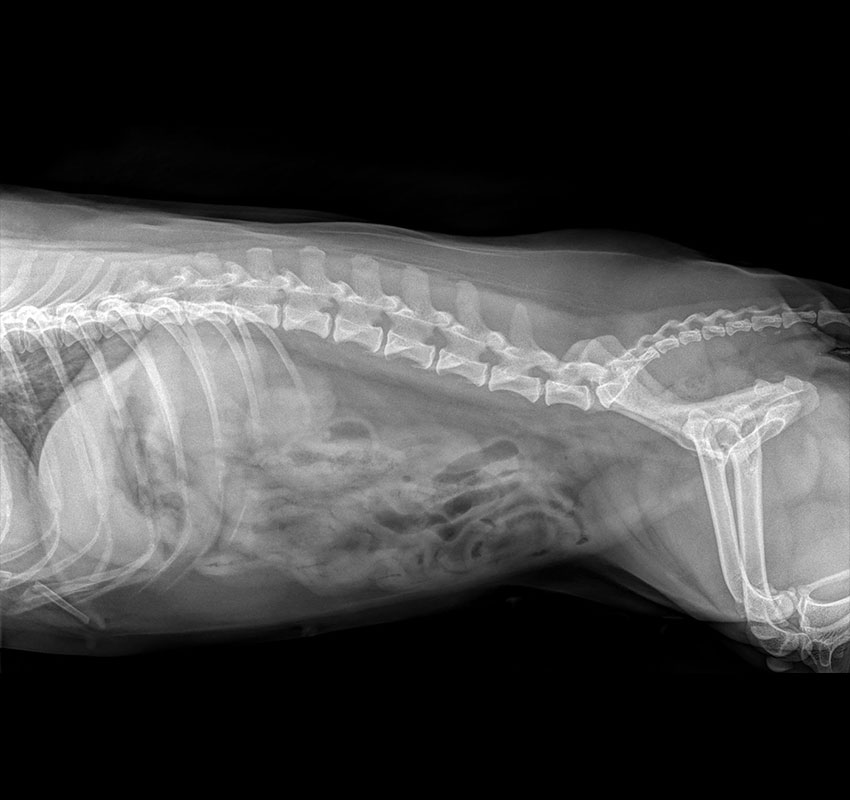

Digital Radiology

Screenings include:

Chest (Thoracic) Radiographs

• Heart Disease (Congestive Heart Failure, Heart Enlargement)

• Lung/Airway Disease (Pneumonia, Chronic Cough, Tracheal Collapse)

• Effusions (fluid in the chest)

Abdominal Radiographs

• Bladder/Kidney stones

• Cancer (Metastatic Screening, abdominal tumors, etc)

• Effusions (fluid in the abdomen)

Orthopedic Radiographs

• Cancer (bone tumors)

• Arthritis Screening

• Post-operative Cruciate Repair